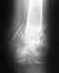

Re: перелом внутренней лодыжки левой голени, левой м/берцовой кости с подвывихом стопы

Уважаемый Доктор!Я понимаю, что речь идёт о моём здоровье,но,к сожалению, действительно возникли огромные проблемы в настоящее время попасть к Вам на лечение!Возможен ли следующий вариант: сейчас я сращиваю переломы,а вправлять и лечить сустав обращусь к Вам чуть позже.Поверте, если бы не было достаточно оснований для такого решения, я бы не стала и спрашивать.Мне 45 лет, я уже большая девочка, всё осознаю.Вот пишу Вам, а сама плачу.Не отказывайте,умоляю!Помогите советом!